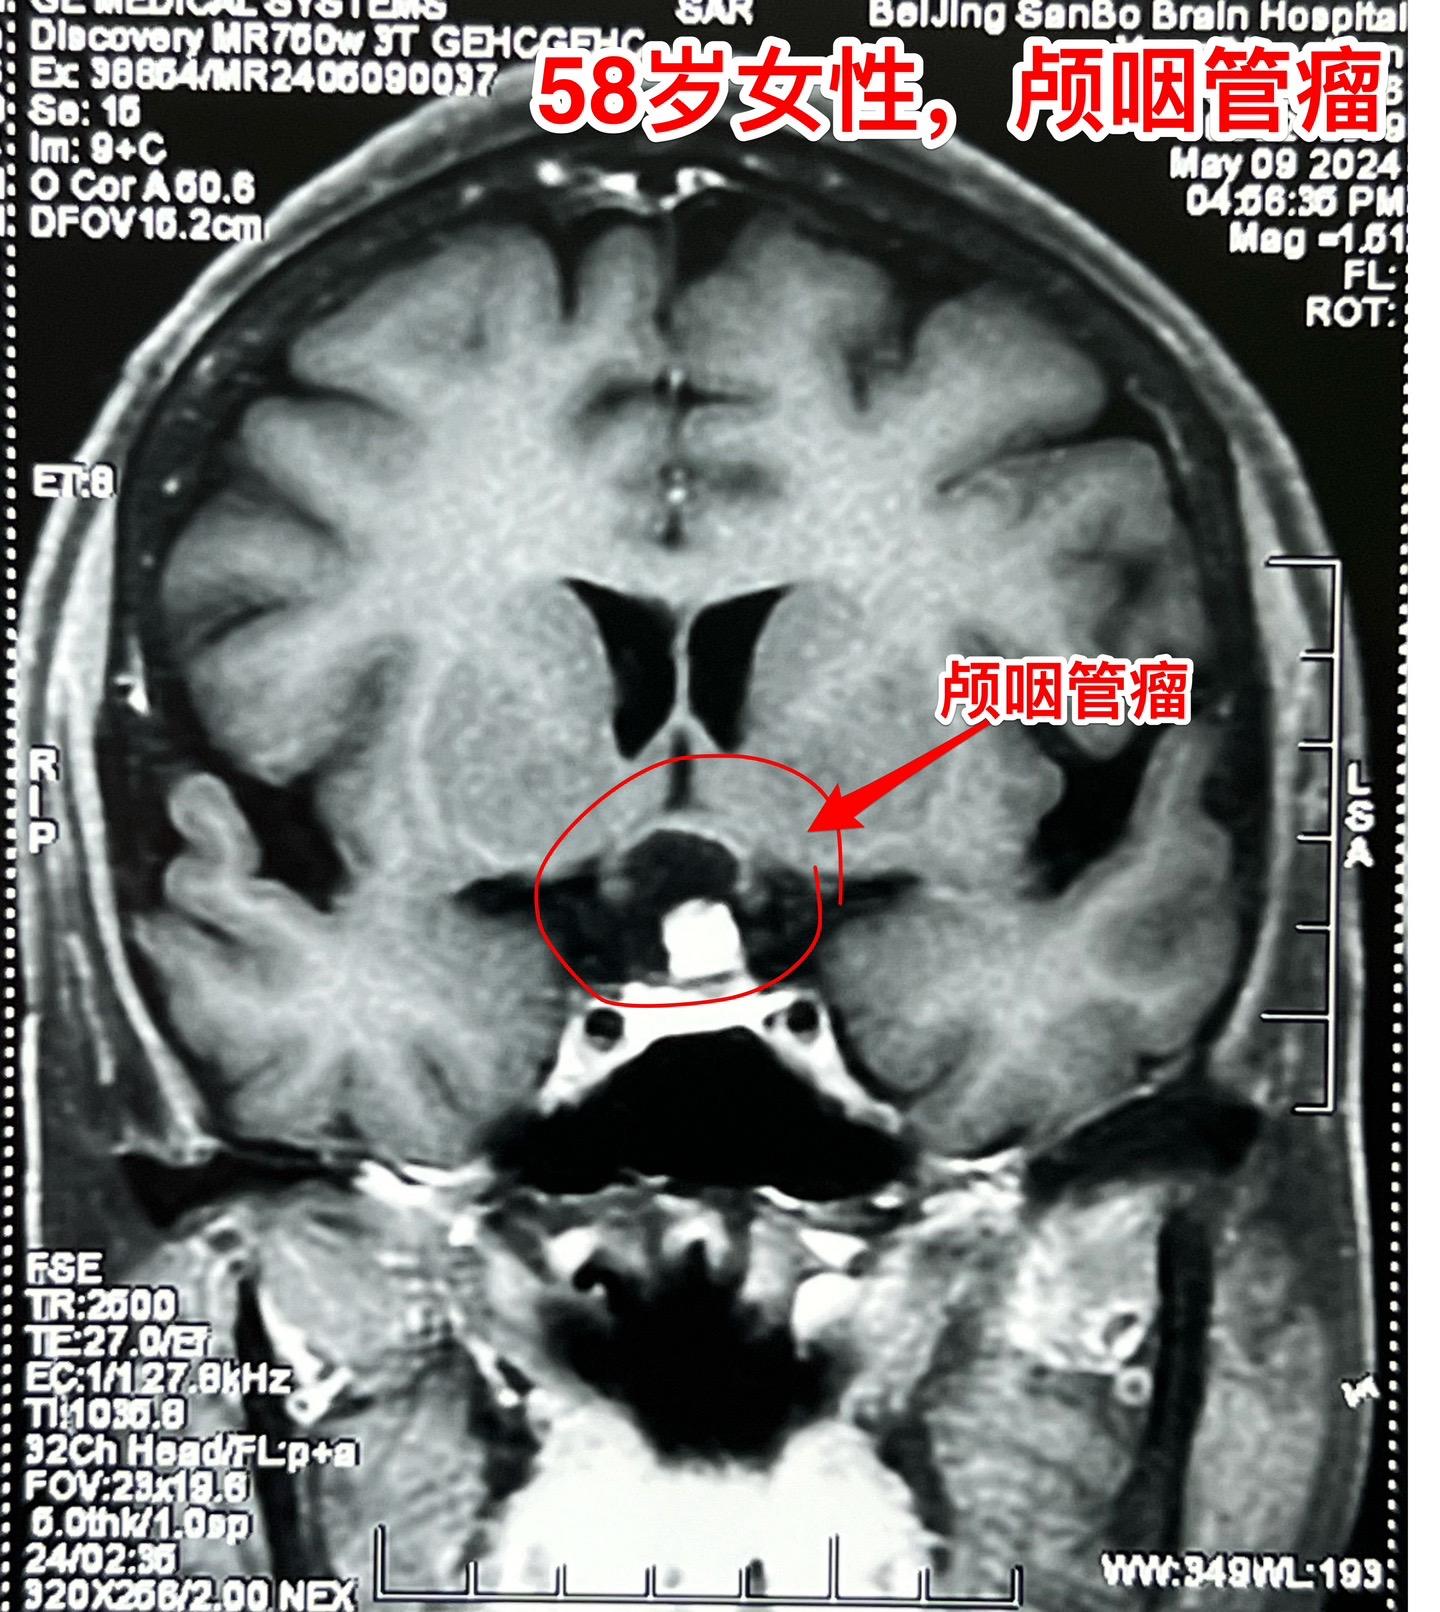

58岁女性视力下降。这是典型的颅咽管瘤。 这样的颅咽管瘤更适合翼点入路:瘤位于鞍上池内,直径约2厘米,乳头型颅咽管瘤。 病人的左眼视力更差,所以选择经左侧翼点入路。肿瘤得到完全切除。视力下降

58岁女性视力下降。这是典型的颅咽管瘤。 这样的颅咽管瘤更适合翼点入路:瘤位于鞍上池内,直径约2厘米,乳头型颅咽管瘤。 病人的左眼视力更差,所以选择经左侧翼点入路。肿瘤得到完全切除。颅咽管瘤视力下降